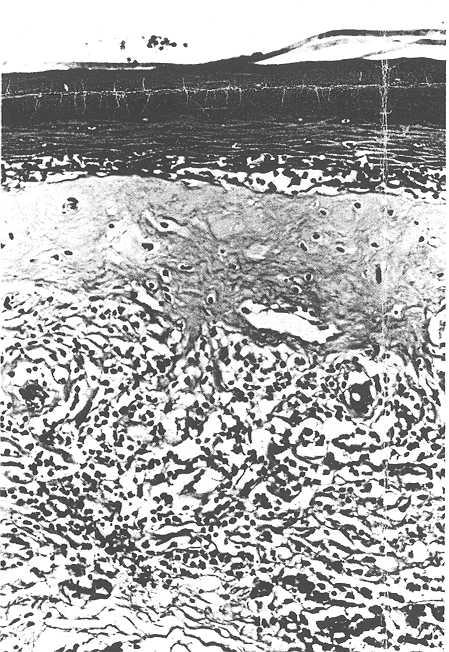

Twenty-one specimens were submitted for histological examination, all but one of which showed the features of Balanitis Xerotica Obliterans (BXO). The histological criteria for this diagnosis was oedema and homogenisation of collagen in the upper dermis, inflammatory infiltration of lymphocytes and histiocytes in the mid-dermis, atrophy of the stratum malpighi and hydropic degeneration of the basal cells (Bainbridge et al., 1971; Lever and Schaumburg-Lever, 1975). A typical example is shown in figure 3. The only atypical finding was that although the stratum malpighi was atrophic in some areas, other parts of the epidermis were of normal width or even acanthotic. A patchy non-specific outer dermal infiltration of chronic inflammatory cells was often present in other parts of the prepuce not affected by BXO. The single specimen not affected by BXO had minimal chronic inflammatory changes in the outer dermis and marked dilation of the lymphatic channels near the inner surface of the prepuce. The foreskins of 11 other boys aged 8 months to 11 years, who had been circumcised for religious reasons, were also examined histologically: none showed the changes of BXO.

Figure 3

Figure 3: Histology of the foreskin of a 7-year old boy with phimosis, showing the features of BXO detailed in the text. (H and E X 120).